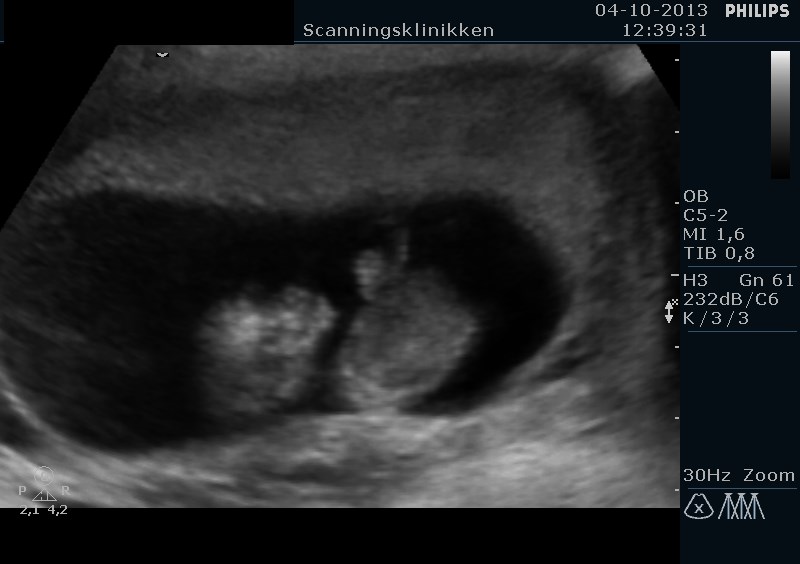

Men se lige hvad vi har set i dag. En lille spire på næsten 5 cm og er 11+5 uger henne med en termin den 20 April <3